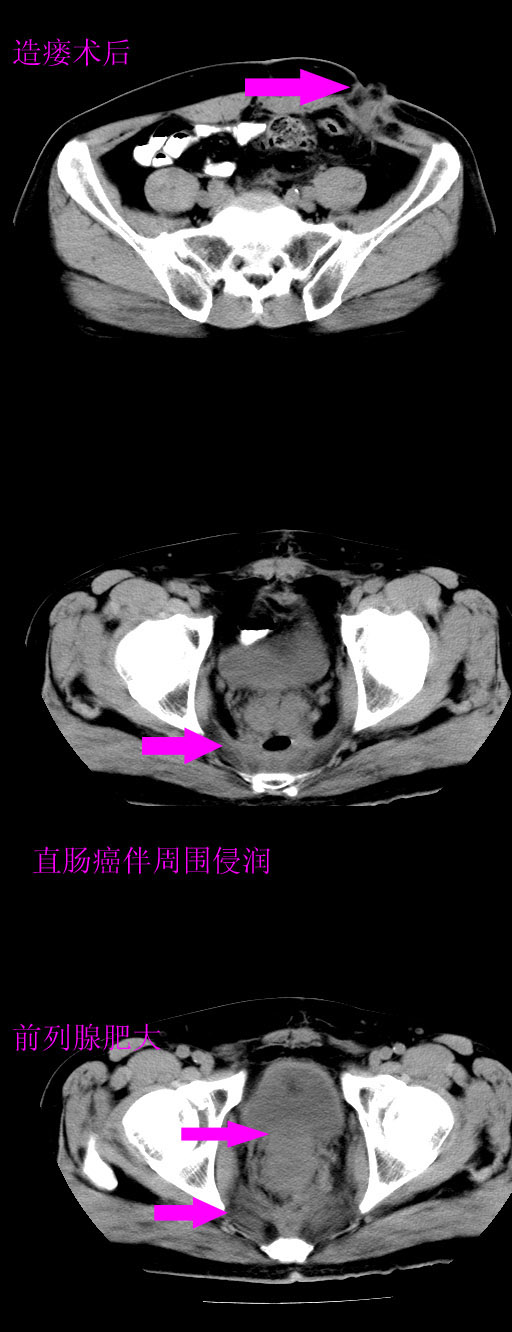

男,66岁,直肠癌术后一个月,化疗前ct检查。

前列腺大,直肠壁厚,造瘘术后

直肠癌造瘘术后改变,周围淋巴结转移

前列腺肥大

直肠癌造瘘术后改变,盆腔多发淋巴结转移

直肠癌造瘘术后改变,直肠周围软组织增厚,盆腔多发淋巴结转移。前列腺肥大。

结肠造瘘术后。

直肠癌周围浸润。

前列腺肥大。